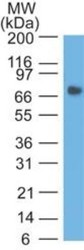

Supportive validation

- Submitted by

- Novus Biologicals (provider)

- Main image

- Experimental details

- Western Blot: CEACAM5/CD66e Antibody (SPM584) - Azide and BSA Free [NBP2-34851] - Western Blot: CEA Antibody (COL-1) [Azide Free] - Analysis of Stomach lysate.